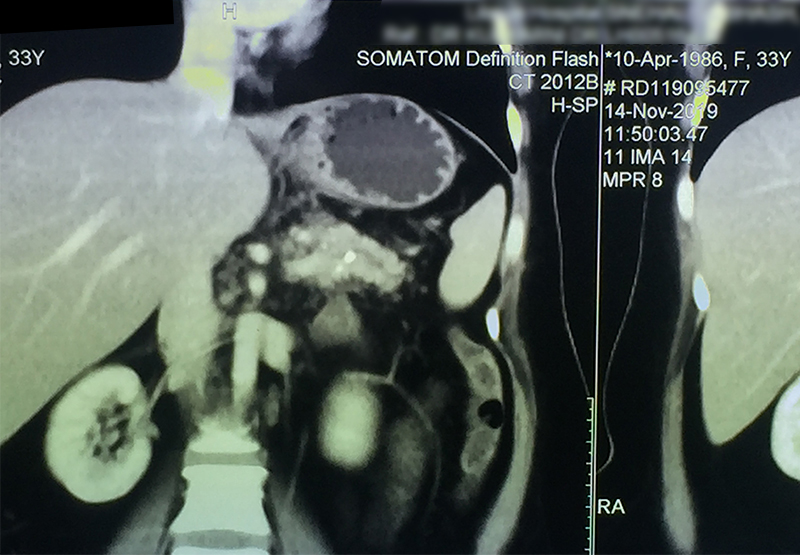

30 year old young lady with chronic pancreatitis, narrowing (stricture) of the pancreatic duct in the head and tail of pancreas and obstructing stone in the tail portion of the pancreatic duct presented to us with a recent attack of mild acute pancreatitis. She had undergone pancreatic duct stenting 3 times before this and stent migrated out of the duct at the last time following which she had acute pancreatitis. She was thoroughly evaluated with CT scan and MRI of abdomen. It showed that the duct had dilated irregularly in head and body of the pancreas and a stone was lodged in the tail. So she had disease both in the head and tail. She underwent a distal pancreatosplenectomy for the tail disease and a pancreaticojejunostomy (Head coring—Frey procedure) for the disease of the head and body of pancreas. She recovered well however the recovery was prolonged due to intra-abdominal infection caused by organisms in the infected pancreatic fluid. Infections originated from the pancreatic stents, were resistant to routine antibiotics and needed expensive drugs for infection control.